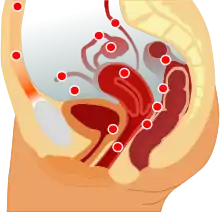

Endometriosis is a disease of the female reproductive system in which cells similar to those in the endometrium, the layer of tissue that normally covers the inside of the uterus, grow outside the uterus.[7][8] Lesions can be found on ovaries, fallopian tubes, tissue around the uterus and ovaries (peritoneum), intestines, bladder, and diaphragm; it may also occur in other parts of the body.[2] Some symptoms include pelvic pain, heavy and painful periods, pain with bowel movements, painful urination, pain during sexual intercourse and infertility.[1][9] Nearly half of those affected have chronic pelvic pain, while in 70% pain occurs during menstruation.[1] Infertility occurs in up to half of affected individuals.[1] About 25% of individuals have no symptoms and 85% of those seen with infertility in a tertiary center have no pain.[1][10] Endometriosis can have both social and psychological effects.[11]

Localization

Most often, endometriosis is found on the:

- ovaries

- fallopian tubes

- tissues that hold the uterus in place (ligaments)

- outer surface of the uterus[2]

Less common pelvic sites are:

Endometriosis may spread to the cervix and vagina or to sites of a surgical abdominal incision, known as "scar endometriosis."[84] Rectovaginal or bowel endometriosis affects approximately 5-12% of those with endometriosis, and can cause severe pain with bowel movements.[85]